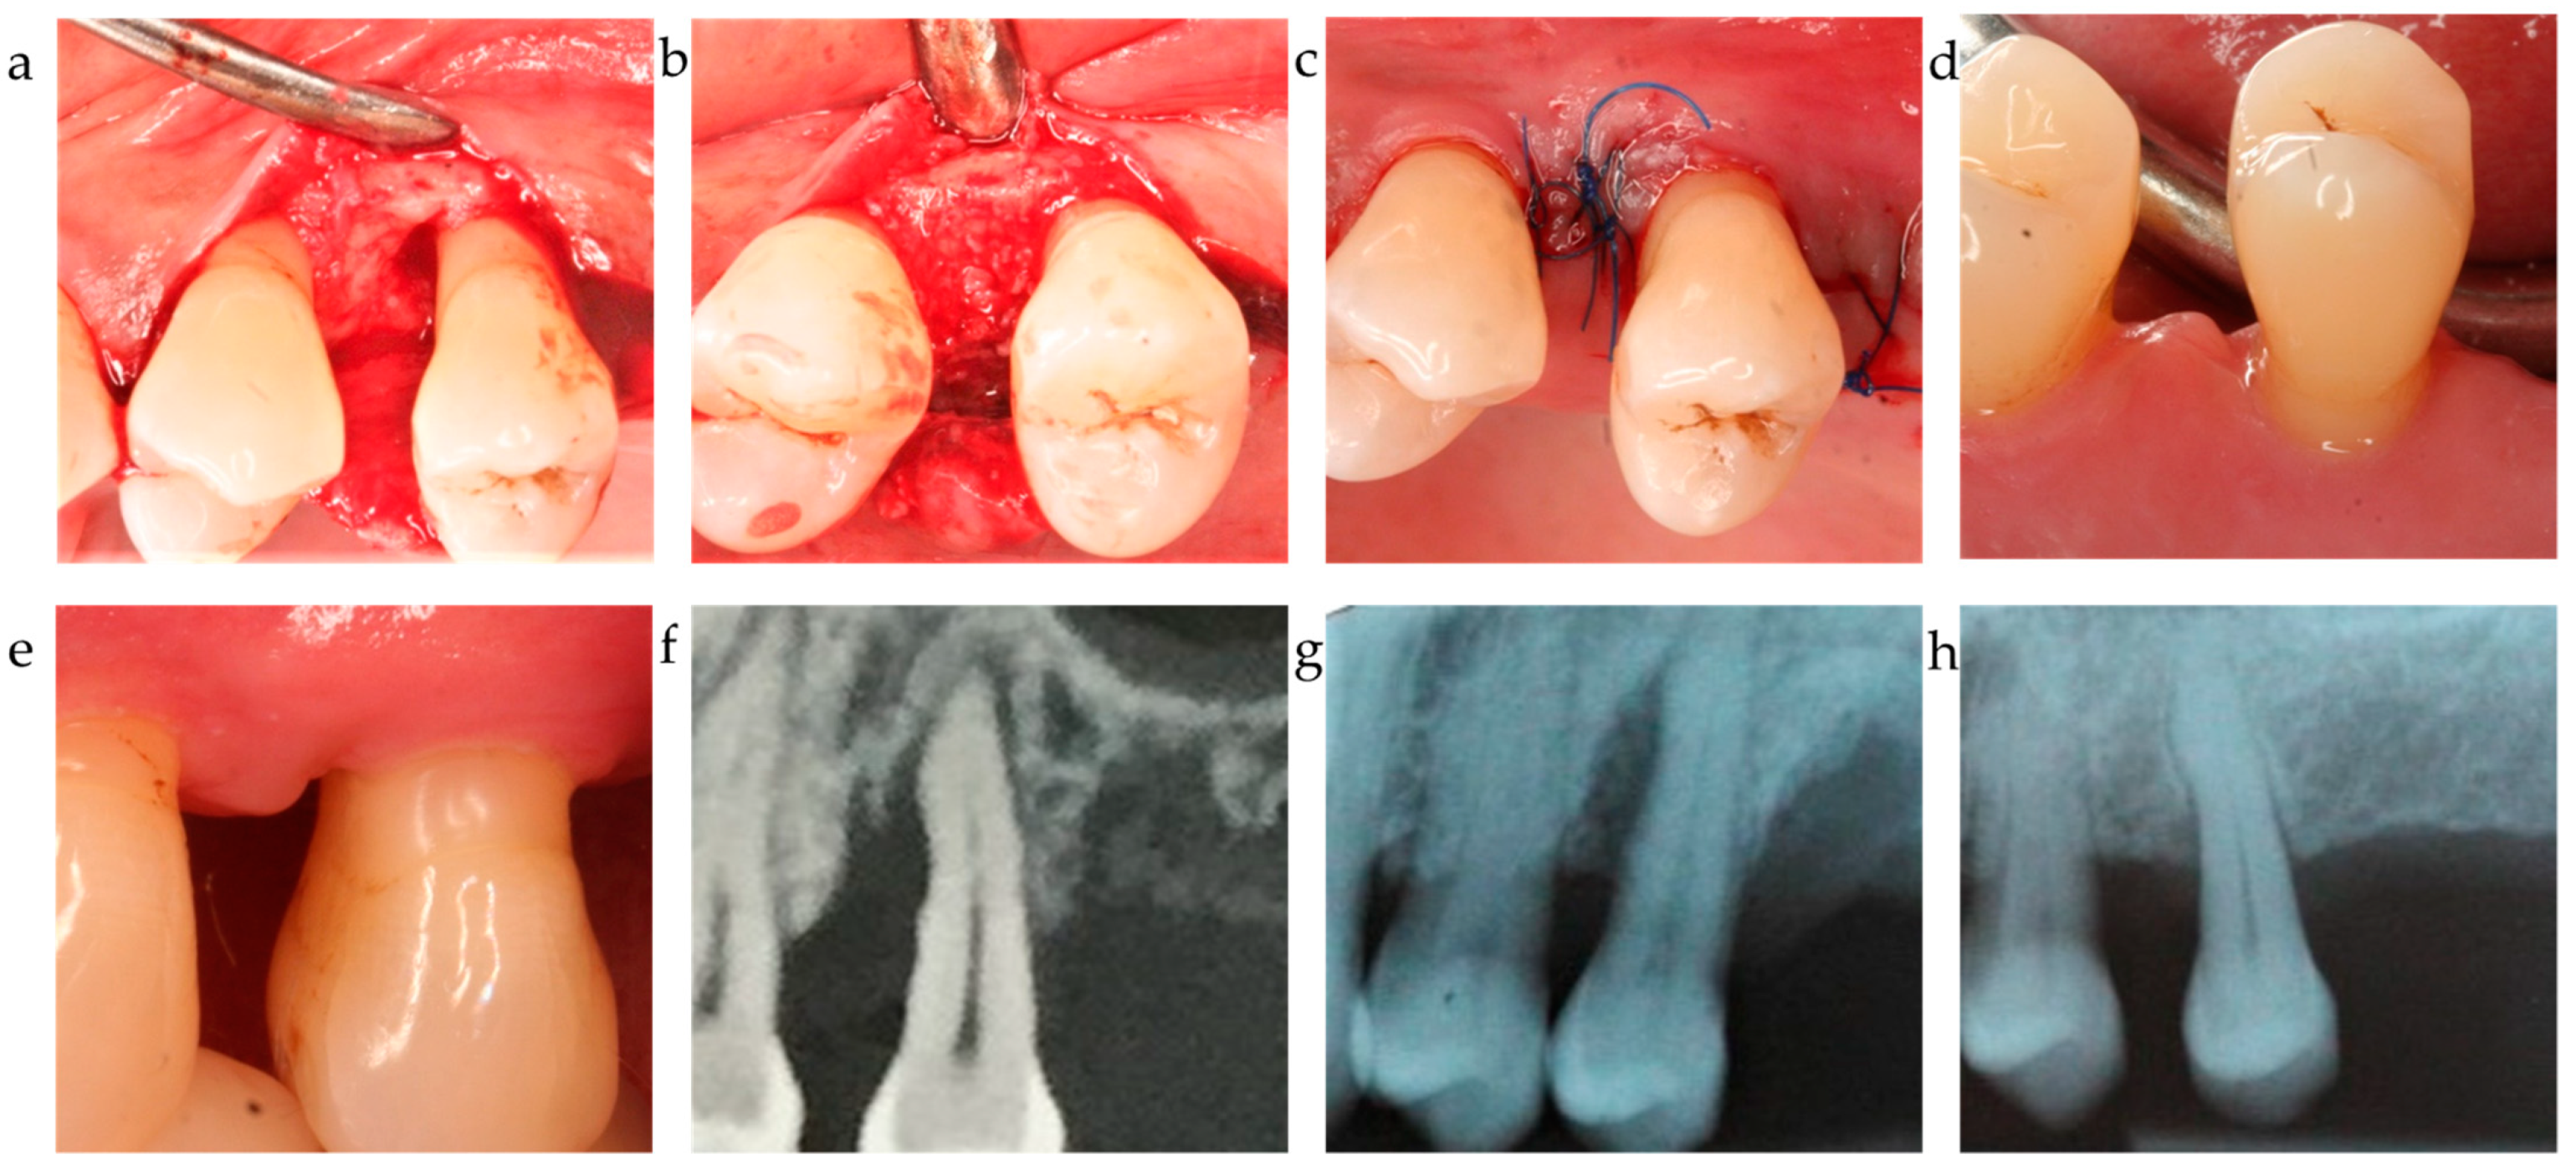

Figure 3.

Center 2 showcase: (a–c) defect extension, defect grafting at surgery, and suture; (d,e) clinical outcome at 12-month exam. (f–h) radiographically observed change in bone level around tooth 25 before surgery and 12 months post-op.